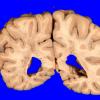

Subcortical Arteriosclerotic Encephalopathy (5)